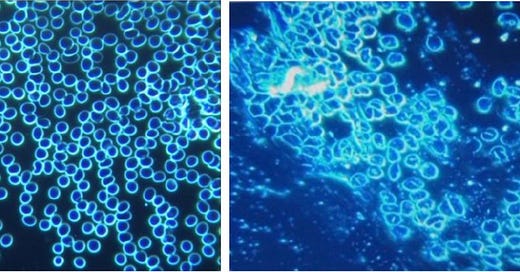

La Dra. Carrie Madej reveló sus hallazgos de Hydra en el Stew Peter's Show el 29 de septiembre de 2021, seguida del sorprendente descubrimiento de la Dra. Zandre Botha de dispositivos médicos microscópicos autoensamblables en la sangre de sus pacientes vacunados. Los glóbulos rojos están peligrosamente deformados y coagulados, cosas que ella dice que nunca antes había visto en sus 15 años como doctora de sangre.

Este estudio recientemente publicado en Italia confirma una vez más las nanoestructuras de autoensamblaje en la sangre de personas inyectadas con C19. Los autores correlacionan los hallazgos de sangre con los síntomas del afectado. Por ejemplo, se discutió este caso:

This was his blood finding:

Estas 4 imágenes ilustran la variedad de fenómenos y objetos inusuales encontrados en la sangre de sujetos vacunados con Comirnaty BioNTech/Pfizer (Cortesía de Helen Krenn)MÁS

These substances, furthermore, “are visible under the dark-field microscope as distinctive and complex structures of different sizes, can only partially be explained as a result of crystallization or decomposition processes, [and] cannot be explained as contamination from the manufacturing process,” the researchers found.

Otros dos hallazgos importantes fueron que las muestras de sangre de los vacunados tenían “cambios marcados” y que se observaron más efectos secundarios en proporción a “la estabilidad de la envoltura de nanopartículas lipídicas”.

Metodología

Los hallazgos de cambios fisiológicos agudos y crónicos en la sangre de las personas inoculadas con las vacunas, discernidos constantemente a través del software de inteligencia artificial, “también se hacen eco de los hallazgos de muchos otros investigadores y respaldan las afirmaciones de contaminación y/o adulteración”, dijo Lindsay.